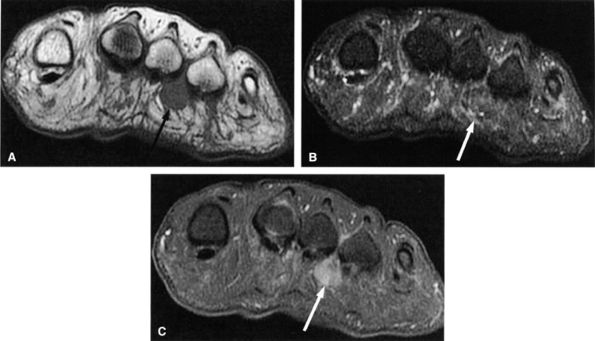

FIGURE 6.53 ● Medial plantar neuropathy. Oblique coronal (A) and axial (B) fluid-sensitive fat-suppressed images of the foot show denervation edema in the flexor digitorum brevis (arrow) and abductor hallucis (asterisk) muscles.

FIGURE 6.54 ● Medial plantar neuropathy. Oblique coronal T1-weighted image of the foot shows denervation atrophy of the flexor digitorum brevis muscle (arrow).

Muscle denervation edema or atrophy of the abductor hallucis and flexor digitorum brevis muscles, seen on MR images of the ankle, is compatible with medial plantar nerve entrapment (Fig. 6.52).

-

Denervation of the first lumbrical and of the flexor hallucis brevis muscle, also consistent with medial plantar nerve entrapment, is better seen on MR images of the foot (Figs. 6.53 and 6.54).